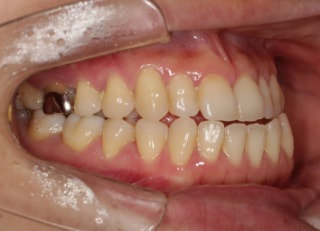

治療前